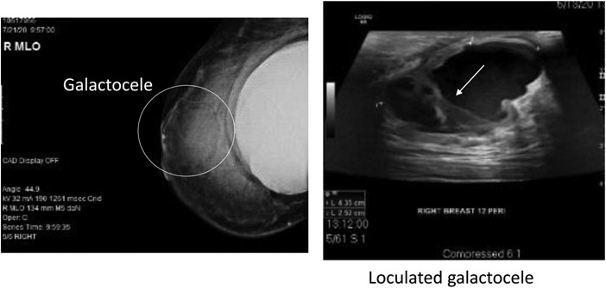

INFECTED GALACTOCELE IN A BREASTFEEDING WOMAN CAUSE BY THE TONGUE TIE AND LIP TIE OF THE BABY Written by: Ernina Rahmatika Muis, MD Case Report Baby A, a female, was the firstborn child of Mr T and Mrs R. Baby A was born via pervaginam delivery with 2,750 grams (g) of birth weight, in a full-term pregnancy on October 3rd 2021. Mrs R exclusively breastfed her baby. During the early weeks of breastfeeding, Mrs R’s breasts became swollen, and then she had three sessions of lactation massages from a midwife. When Baby A was 5 months old, Mrs R frequently complained of marble-sized lumps on both breasts, that disappeared and recured. The lumps disappeared a few days while breastfeeding the baby and recured at a discrete spot. Mrs R was a working mother. The Baby received expressed breastmilk from a teat bottle. Meanwhile, when she was at home after work or during days-off, the baby breastfed directly from the mother or having direct breastfeeding (DBF). Mrs R registered to the lactation clinic for the first time on 8 May 2022. She complained having a lump in her right breast that had existed for the past 2 months. Initially, the lump was about the size of a marble, then rapidly enlarged over several weeks to the size of a chicken egg and had remained to the date of first admission to the lactaion clinic. Mrs R also had a fever that subsided after taking paracetamol, while no antibiotics were taken. Based on the anamnesis, a family history of breast cancer was obtained from Mrs R’s grandmother, and she was worried that her lump might be a breast cancer. Based on a physical examination, a lump of size 6x5x5 cm or about the size of a chicken egg on the right breast with a firm border was palpable at direction of 10 o’clock. The lump was mobile when the lactation doctor attempted to palpate the area. Redness or faint erythema appearance was present on the lump’s surface. There was minimal tenderness and minimal fluctuation. When the Baby was 7-month and 5-day old, her weight was 8,300 g and the weight gain was 25.81 g/day and the baby’s nutritional status was normo weight. The baby had complementary food, strained rice porridge, twice daily. The baby also had snacks three times a week. During a physical examination by a lactation medical doctor, it was found that the baby had tongue tie, the medial type, and lip tie, grade 4. Based on a direct breastfeeding observation, it was found that the baby’s suction reflex was not optimal, the baby latched poorly to the breast, and was easily distracted during breastfeeding. While breastfeeding, the baby often slipped from the breast, and finished breastfeeding before emptying the breast(s). Based on the history taken and physical examination, the lactation doctor explained to the patient that the cause of the recurring lump (galactocele) was that the baby latched poorly and inadequately. Poor latching to the breast was caused by the baby’s tongue tie and lip tie, and also by the use of a teat bottle during the working hours of the mother. For treating the tongue tie and lip tie, the lactation doctor explained the procedure of simple frenotomy to both Mr T and Mrs R. The mother was prescribed painkiller, antibiotic, and Vitamin D3. An ultrasound examination of the breast was also required to rule out any possibility of breast abscess and cancer. The lactation doctor also counselled Mr T and Mrs R for complementary food in order for the baby to have the proper and subtle kind of complementary food. It was also mandatory that the baby stop using teat bottle hence the parents had counselling session for working mothers. The counsellor also trained the caregiver to give expressed breastmilk using cup. Mrs R’s right breast lumps was 6x5x5 cm and at direction of 10 o’clock. The second admission to the lactation clinic was on May 10th 2022. The Baby was 7-month and 7-day old and the weight was 8300 g. The ultrasound examination was performed a day before the admission (9 May 2022). There were no additional complaints from Mrs R or the baby. Redness on the breast disappeared, also the lump size stayed the same. According to the ultrasound examination report, the following findings were obtained: Suggestive abscess formation at the superolateral quadrant of the right mammary, isoechoic lesion with a cystic component at the superomedial quadrant of the left mammary dd/galactocele and bilateral axillary reactive lymphadenopathy. At this visit, Mr T and Mrs R agreed to perform a simple frenotomy for the baby. The mother learned how to do tongue and lip exercise, physical therapy done to the baby that is essential after frenotomy was performed. The lactation doctor also suggested a cold cabbage compression over the right breast to reduce the lump and the pain. The mother and baby dyad admitted to the ward for further treatments needed. Ultrasound image, May 9th, 2022 Right breast Left breast In ward, May 10th 2022, the surgeon visited the mother in ward. By the previous history taken, physical examination and ultrasound examination, it was decided to treat Mrs R as an outpatient. Mrs R was allowed to discharge and it was no longer necessary to carry out any surgery as there was a good response to the previous antibiotic treatment. The diagnosis was infected galactocele and it didn’t require any surgical treatment. The surgeon also provided some further oral therapy as an outpatient care. It is essential that Mrs R continue to breastfeed her baby on both breasts, as the optimum suction of the baby would empty the breasts and thus shrink the galactocele. The lactation doctor also suggested applying a cold cabbage compression if it feels painful around the lump. On the third admission , May 13th 2022, the baby was 7-month and 12-day old. Mrs R came to an internationally certified lactation consultant paediatrician. Mrs R felt the lump shrunk. At this point, the baby weight gain was 13.33 g/day since her second visit. By the history taken, it was found that the lip exercise was not perfomed properly, hence the scar tissue was formed and found at physical examination, causing her weight gain was insufficient. The baby subsequently underwent a re-incision (frenotomy) of the lip tie to achieve optimal suction and the weight gain would be optimal. On the fourth admission, May 20th 2022, the baby was 7-month and 19-day old. Mrs R came for a follow-up visit. The baby did not gain anyweight, even by that time the weight reduced by 75 g since the third visit. The baby experienced fever, cough and runny nose over the past week. The baby was prescribed Vitamin D3. The mother also continued taking Vitamin D3 and the lump decreased by size. Mrs R also said that her baby latched better and might be optimal as she felt her breasts emptied after breastfeeding sessions. On the fifth admission, June 3rd 2022, the baby was 8-month and 3-day old. Mrs R came for a follow-up visit. At this time, the baby weight was 8290 g, the weight gain was 1.78 g/day since the fourth visit. The lump on the mother left breast reduced almost to none. The baby A had stopped drinking from a teat bottle. When the mother was at work, the baby had expressed breast milk from a cup. However, the baby’s complementary food needed to be adjusted in terms of its texture and frequency. Therefore, the mother was counselled for a 4-star complementary food WHO recommendations by the lactation doctor and was advised that the baby had aditional chicken egg in meal, known as egg therapy for the weight gain to be appropriate and optimal. In the last follow-up session held by the lactation doctor, the baby was 11-month-old with a weight of 9700 gr (increased by 21.06 gr/day from the birth weight). Baby A had already consumed some complementary foods, which were textured as family meals. The main meal frequency was 3 times a day, while snacks were given once to twice a day. At this point, the mother fed the baby at least one chicken egg each day and did not neglect supplementary fat intake. The baby weight gain sufficiently increased every month. There was no breastfeeding and complementary feeding problem. Baby A was healthy with a good nutritional status, and still had only direct breastfeeding sessions when the mother stayed at home. When the mother was at work, the expressed breastmilk was given to the baby using cup adherently. As the father supports the mother continuously, the mother felt excited and optimistic to continue breastfeeding until the reached 2-year-old. The baby weight graph DISCUSSION Galactocele is a benign lump that presents specifically within a female breast. It is a cyst filled with breast milk that occurs due to a blockage of the mammary duct or any obstruction at the lactiferous duct. 1 A galactocele develops when ductal narrowing obstructs the flow of milk to the extent that a significant volume of obstructed milk collects in a cyst-like cavity. Galactoceles can range in size from small (1–2 cm) to very large (>10 cm). Galactoceles present as moderately firm masses that gradually or rapidly increases in size over time. The size may fluctuate throughout the day, with a temporary decrease after breastfeeding. It may be uncomfortable, but is generally not as overtly painful as an abscess and does not have associated erythema or systemic symptoms unless it becomes infected galactocele. Ultrasound will show a simple or loculated cystic fluid collection. On occasion, image-guided aspiration may be performed to confirm the diagnosis. 2 In this case report, Mrs R’s lump was initially as large as a marble and persisted for 2 months and then rapidly enlarged over a week to the size of a chicken egg that persisted for 1 week. The lump was minimally painful upon pressure, had a faint red appearance on its surface, minimally fluctuated on pressure, and caused fever that lasted for a day. According to those findings, it leads to a conclusion that the lump was benign and not a breast cancer (Ca mammae) since the lump was mobile when it was moved by hand and there were no typical signs of breast cancer such as peau d’orange, nipple retraction or pus and blood came out of the nipple. Therefore, the diagnosis in this case was concluded as pre-abscess infected galactocele. The mechanism of direct breastfeeding for the baby to suckle the breast is a complex process. Initially, the baby must be able to seal the breast by folding the lips outwards, allowing no air flows into the mouth. Following that, the baby will grasp the breast by using the tongue and then press the breast towards the palate, the upper lining of the mouth cavity. Afterwards, in a rhythmic motion, the baby will continuously press the breast towards the palate and lower the tongue down to give it a relatively more negative vacuum, before finally the breastmilk comes out.3 Nevertheless, some babies with Tongue Tie and Lip Tie are unable to optimally empty the breast when they latch at the mother’s breast. That may cause a swollen breast or palpable lumps or bumps in certain areas of the breast. As per Mrs R’s case, due to Baby A’s non-optimal suction, the breast emptying was not optimal. As the result, Mrs R often experienced galactocele in certain areas of the breast. The cause of non-optimal suction in Baby A is due to the tongue tie and the lip tie. The lingual frenulum is a mucous membrane connecting the underside of the tongue with the floor of the mouth. This tissue has various appearances, can be thin or thick, long or short. When the lingual frenulum is short, fibrous, tight, or positioned too far forward, it limits the normal range of motion of the tongue and affects oral function. In such cases, ankyloglossia, or tongue tie is identified. 4 In addition to tongue tie, breastfeeding problems can also be caused by lip tie. Lip tie is a string or frenulum at the top of the lip that attaches to the upper jaw. This frenulum has no muscles and only consists of a membrane. If the frenulum is attached to the bone or upper gum, it can cause limited movement of the lips during breastfeeding. Flange-out lip position is needed in the breastfeeding process so that the baby’s mouth can create a vacuum or high negative pressure so that the baby can suck well and the transfer of the milk can be optimal. Flange-out lips also stimulate the oxytocin chain release, which causes the optimal release of breast milk from the mother’s breast. A baby’s lips that are not engorged when feeding to the breast can cause breastfeeding complaints, such as pain and sore nipples.5 Parents received a full explanation about tongue tie and frenotomy and gave written informed consent prior to the procedure. In preparation for frenotomy, the baby was swaddled to immobilize the arms and legs and laid supine on the examination table. An assistant helped by holding the head still while the operator lifted the tongue with a finger to locate the frenulum.6 The frenulum was then snipped with blunt-ended sterile scissors, and sterile gauze was used to stop the bleeding. The tongue-tie was assessed as completely released if a neat diamond shape was visible with no palpable tissue remaining to restrict tongue movement. We favored not using general anesthesia to perform the procedure because this is likely to add delays in breastfeeding. Immediately after frenotomy, the mother was asked to breastfeed her baby for reevaluation of latch and improvement. The mother was taught how to perform tongue exercises to prevent reattachment. A follow-up visit was scheduled 3 days later to assess for complications and to evaluate the baby weight gain. A further review was scheduled 1 week later and continued every week after as necessary until the breastfeeding dyads’ course was considered as satisfactory.7 Following the frenotomy performed on Baby A, Mrs R’s felt that the lump was reduced in size, the faint redness appearance diminished and the breast became painless. Mrs R felt that her baby had a stronger suction and was able to empty the breast(s) after breastfeeding sessions. The complementary food and the additional egg therapy also affected the baby’s growth and development. The complementary food appliance is in accordance to WHO recommendations. Baby A’s weight gain was also favoured and was found to be in a good nutritional status until the last follow-up visit. The following are 10 principles of infant complementary feeding according to WHO recommendations, (1) Breastfeed for 6 months, then give complementary feeding while continuing to breastfeed the baby. (2) Continue to breastfeed the baby until 2 years of age (on demand). (3) Implement active-responsive feeding (4) Ensure food hygiene and proper food storage. (5) Start the feeding with a small amount and gradually increase it. (6) Gradually adjust the texture of the food as the baby grows. (7) Increase the frequency of feeding as the baby grows. (8) Provide a variety of foods to fulfil the baby’s nutritional intake. (9) If indicated, use fortified foods or supplements. (10) Consider the feeding method if the baby is unwell. 8 In this particular case, we can conclude that galactocele, which is frequently experienced by mothers, is often caused by tongue tie and lip tie in infants. Through a simple frenotomy on the baby, along with the mother’s oral therapy and complementary feeding according to WHO standards, the baby can grow and develop optimally and the mother can continue to breastfeed for up to 2 years of age. BIBLIOGRAPHY De jong, Sjamsuhidajat. Buku Ajar Ilmu Bedah. EGC. Jakarta. 2010Mitchell K, et al. Academy of Breastfeeding Medicine Clinical Protocol #36: The Mastitis Spectrum, Revised 2022. 2022 ; 365Praborini A, Wulandari RA. Anti Stres Menyusui. Kawan Pustaka. Jakarta. 2019Clay W, Hoover. The Breastfeeding Atlas Sixth Edition. United States of America. 2013 : 14Cole M. Tongue and Lip Tie: A Comprehensive Approach to Assessment and Care. Powerpoint presentation. 2017Sunil Kumar, P., Raja Babu, p., Jagadish Reddy, G., & Uttam, A. (2011). Povidone iodine – Revisited. Indian Journal of Dental Advancements, 3 (3). 617-620Praborini A, Purnamasari H, Munandar A, Wulandari RA. Early Frenotomy Improves Breastfeeding Outcomes for Tongue-Tied Infant. United States Lactation Consultant Association. 2015; 6 (1): 9-15.Direktorat Gizi Masyarakat Ditjen Kesehatan Masyarakat Kementrian Kesehatan Republik Indonesia. Manajemen Makanan Pendamping ASI. 2016